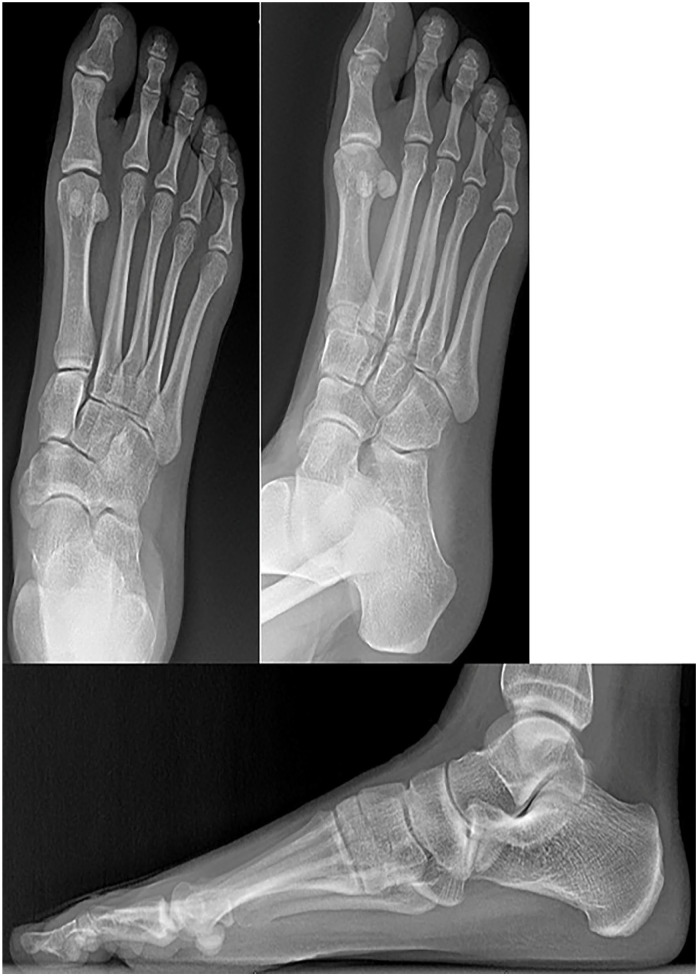

Background: An accessory navicular is a supernumerary ossicle located medial to the navicular bone, typically within the substance or insertion of the posterior tibial tendon, and can be a source of pain and dysfunction in active individuals.

Abstract Image